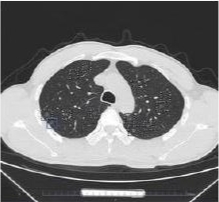

肺结节人工智能筛查影像

近日,绍兴37岁的胡先生出现咳痰、胸闷等症状,在体检时被查出,两肺长了557个磨玻璃结节,其中高危26个,弥漫分布于两肺,以磨玻璃密度为主,毫无规律、毫无特征,最大的12mm。综合临床各项检查数据与资料,对胡先生的诊断最终倾向早期肺恶性肿瘤(早期肺腺癌可能)。